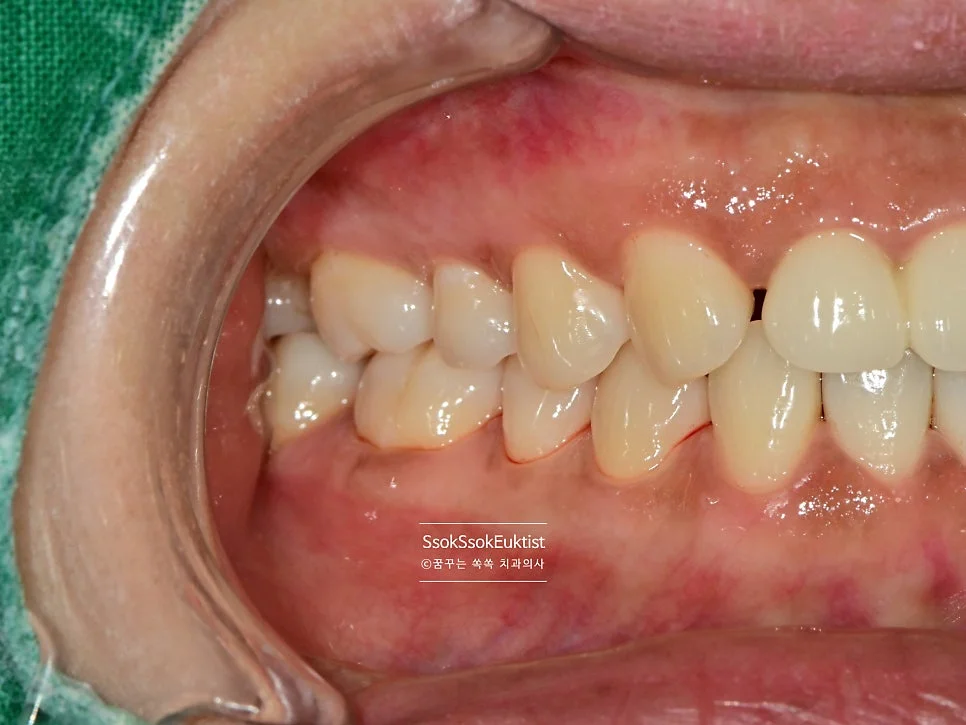

스케일링 전 구강 정면 임상 사진

구강 정면 — 관리가 조금 필요해 보이지만…

이 증례에서도 사진을 보면 구강 내 관리가 조금 필요해 보입니다만,